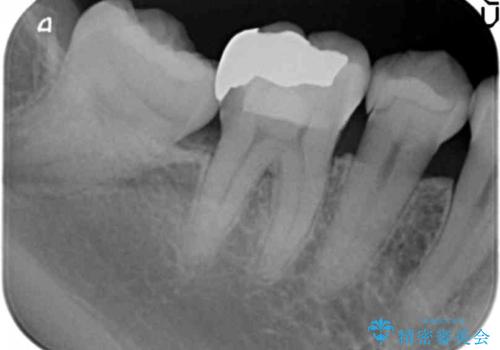

- 他院で虫歯治療に伴い初めての神経の治療を行ったところ、神経の治療自体10回以上通った上に抜歯と言われたとのことでした。

初診時には歯肉が腫れており、膿が出ている状態でした。

また、根の詰め物が根尖孔外(根の先の外の骨の部分)に盛大に漏れ出しており、歯周ポケットと根尖病巣が交通しているような状態でした。

被せ物を外したところ、歯が大変薄くなって割れており、残念ながら残すことはできないと説明しました。

初めての根の治療には見えないくらい、かなり歯が削ってあり、薄くなっていて割れても仕方ない状態でした。前の状態を見ていないので何とも言い難いですが、他の歯に比べこの歯だけ極端に状態が悪かったです。